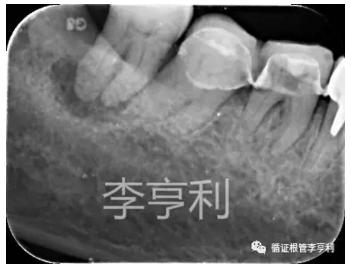

【轉診原因】:46器械分離

【病史】:46活髓牙,行冠修復后逐漸出現(xiàn)冷熱刺激痛及自發(fā)痛,轉診醫(yī)生診斷該牙為不可逆性牙髓炎,并開始根管治療。在疏通MB根的途中,發(fā)現(xiàn)#15 K 銼分離致根管無法疏通,隨后轉至我處

【輔助檢查】:遠中角度投射根尖片,見斷械影像移向近中,故判斷器械分離于近中頰根,根尖周未見明顯異常 (詳見CBCT┃如何使用傳統(tǒng)根尖片)

【術前診斷】:46根管已開始治療,根尖周正常組織,伴發(fā)器械分離 (previously initiated treated with normal apical tissues, complicated by separated instrument)